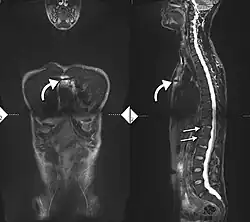

34-year-old male with AS. Inflammatory lesions of the anterior chest wall are shown (curved arrows). Inflammatory changes are seen in the lower thoracic spine and L1 (arrows).